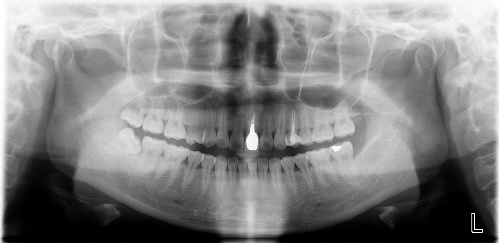

1、根管治疗是分牙位收费

一般情况下分为3大类:前牙、前磨牙(双尖牙)和磨牙。其中前牙根管治疗价格最低,然后就是前磨牙,后磨牙最贵。

2、根管治疗按牙根收费

一般情况下我们的前牙只有1条牙根,而我们的磨牙则有3-4条牙根,因此治疗起来也会更麻烦更耗时间。

3、根管治疗按复杂程度收费

一般情况下初次根管治疗比二次光管治疗费用相对较低,第二次进行根管治疗不仅手术难度大,所以二次根管治疗费用会更高。